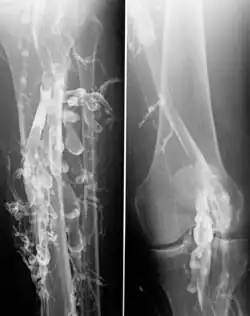

A flebografia, também conhecida como venografia, é um procedimento no qual um raio-x das veias é realizado após a injeção de um contraste numa veia, usualmente do pé. O contraste deve ser injetado constantemente através de um catéter, o que configura o procedimento como invasivo. O pioneiro da flebografia foi o professor e cirurgião João Cid dos Santos (1907-1975).

Era um exame usado para diagnosticar trombose venosa profunda, porém atualmente já não é usado para este fim pois a Ecografia e o doppler vieram facilitar o diagnóstico pela precisão, conforto para o doente e menor custo. Pode eventualmente ser usado para fins de investigação ou em certos casos de malformações venosas.[1]